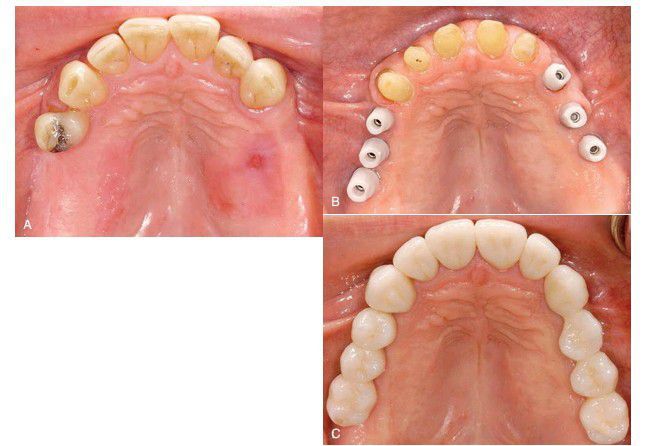

Restoration of bilateral posterior edentulous maxilla

. (A) Pretreatment view. (B) Six zirconia abutments in place for two three-unit fixed partial dentures and five natural teeth prepared for individual all-ceramic crowns. (C) Final restorations in place.